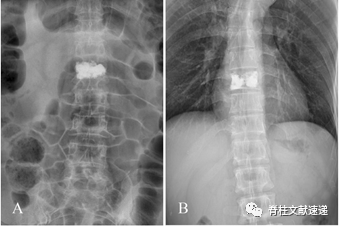

图注:PVP术后X线结果显示骨水泥分布较为满意;

图注:PVP术后X线结果显示骨水泥分布较差;